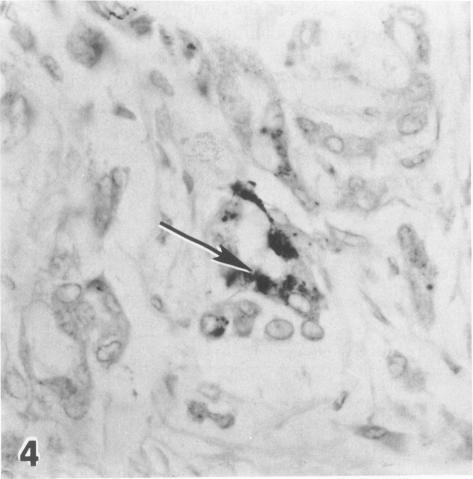

The correct distinction between malignant mesothelioma of the pleura and adenocarcinoma of the lung has become increasingly complex, with a variety of histochemical, immunohistochemical, and ultrastructural studies to be performed on biopsy material. The reliability of immunohistochemical studies has been hampered by the use of polyclonal antisera to "carcinoembryonic antigen (CEA)" and keratin. Hybridoma technology now offers monoclonal antibodies (MAbs) in unlimited quantity and standardized quality to selective ranges of specific antigenic determinants. MAb B72.3, generated against a membrane-enriched fraction of human metastatic breast carcinoma, was used to distinguish malignant mesothelioma of the pleura from adenocarcinoma of the lung in tissue sections and was compared in terms of diagnostic utility with polyclonal anti-keratin and anti-CEA to make the same distinction. Reactivity with MAb B72.3 in at least 10% of tumor cells or more was noted in 19 of 22 adenocarcinomas of the lung (P greater than 0.0001), whereas none of the 20 cases of malignant mesothelioma demonstrated comparable reactivity. Furthermore, MAb B72.3 showed no reactivity with benign mesothelial proliferations. MAb B72.3 thus appears to be an appropriate diagnostic adjunct capable of discriminating between these malignancies.